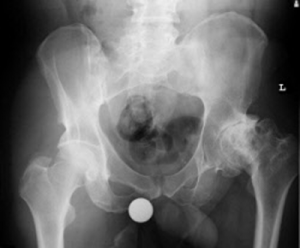

pre-operative